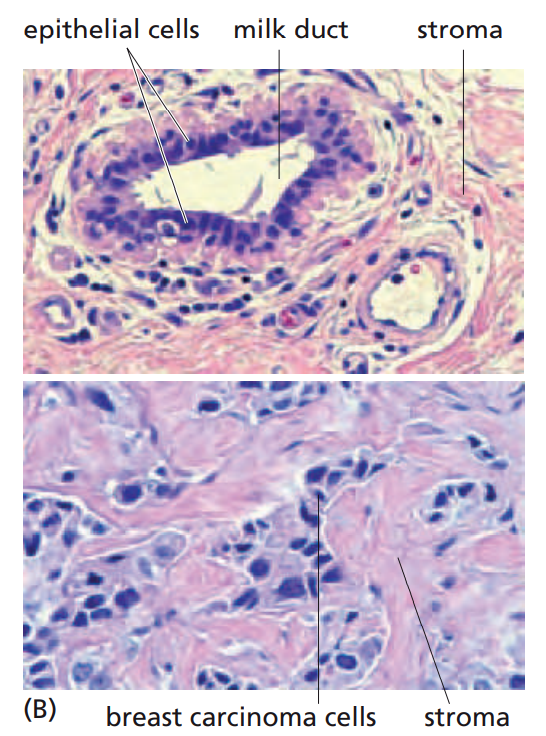

人类大多数肿瘤来源于上皮组织。上皮细胞使构成体腔、管道和表皮的线性排列的层状细胞。在上皮细胞层之下是基底层(也叫基膜);基底层则把上皮细胞与下面起支持连接作用的间质层细胞分开。

上皮细胞孵育产生人类最常见的肿瘤,称之为癌。80%以上的癌症相关死亡都是这类肿瘤引起的。其中包括胃肠道上皮细胞层来源的肿瘤,胃肠道又包含口腔、食管、胃、小肠和大肠,以及皮肤、乳腺、胰腺、肺、肝、卵巢、胆囊、和膀胱来源的肿瘤。

绝大多数恶性肿瘤可被分为两类,分别反映出与上皮细胞相关的两个重要的生物学功能。一些上皮细胞层的主要作用使封闭腔穴或管道的表面并且保护其下层的细胞,由这类上皮细胞发展而来的肿瘤叫做鳞状细胞癌,如皮肤和食道的上皮细胞。还有许多上皮组织中存在特殊的具有分泌能力的细胞,它们可以释放分泌物到自身形成的导管或腔穴中,这种上皮组织衍生的癌称为腺癌,如肺和胃的上皮细胞。多数情况下,两种类型的癌细胞共存于这些器官的肿瘤中。